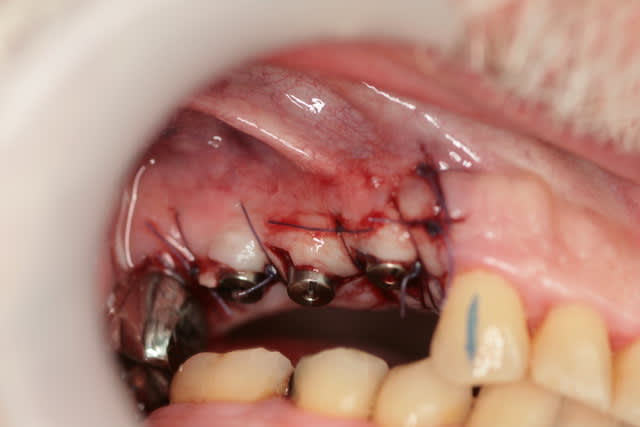

ce matin trois petits implants et mise en place des vis de cicat simultané

technique de palacci et à priori je suis assez content de moi

encore merci monsieur noah dont j'ai raté le nananiv ya pas longtemps BA tout de même olivier

Img 5669 umwmqv - Eugenol

Img 5663 ojygs4 - Eugenol